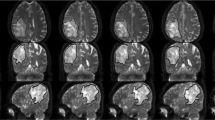

Diffusion spectrum imaging was performed in 122 meningiomas (30 males, 13–84 years), which were divided into 31 high-grade meningiomas (HGMs, grades 2 and 3) and 91 low-grade meningiomas (LGMs, grade 1). The histogram features of multiple diffusion metrics obtained from diffusion tensor imaging (DTI), diffusion kurtosis imaging (DKI), mean apparent propagator (MAP), and neurite orientation dispersion and density imaging (NODDI) in the solid tumours were analysed. All values between the two groups were compared with the Man-Whitney U test. Logistic regression analysis was applied to predict meningioma grade. The correlation between diffusion metrics and Ki-67 index was analysed.

The DKI_AK (axial kurtosis) maximum, DKI_AK range, MAP_RTPP (return-to-plane probability) maximum, MAP_RTPP range, NODDI_ICVF (intracellular volume fraction) range, and NODDI_ICVF maximum values were lower (p < 0.0001), whilst the DTI_MD (mean diffusivity) minimum values were higher in LGMs than those in HGMs (p < 0.001). Amongst the DTI, DKI, MAP, NODDI, and combined diffusion models, no significant differences were found in areas under the receiver operating characteristic curves (AUCs) for grading meningiomas (AUCs, 0.75, 0.75, 0.80, 0.79, and 0.86, respectively; all corrected p > 0.05, Bonferroni correction). Significant but weak positive correlations were found between the Ki-67 index and DKI, MAP, and NODDI metrics (r = 0.26–0.34, all p < 0.05).